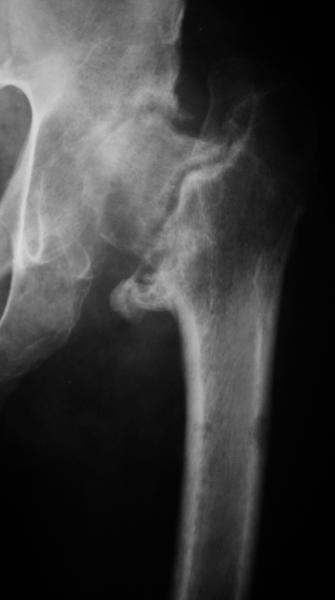

Еще пара фото, ситуация несколько иная, задачи те же, открытое вправление застарелого вывиха в 2002, молодой возраст. Сейчас госпитализирована для эндопротезирования.

Насчет 8 см согласен с А.Н. Челноковым, это наверное ортопедическое за счет приводящей, сгибательной контрактуры и, возможно, колена. на ликвидацию укорочения у нас обычно уходит около 2-х нед. снимки в приложении, возможно не очень показательные, но других с ходу не нашел, завтра еще поищу.